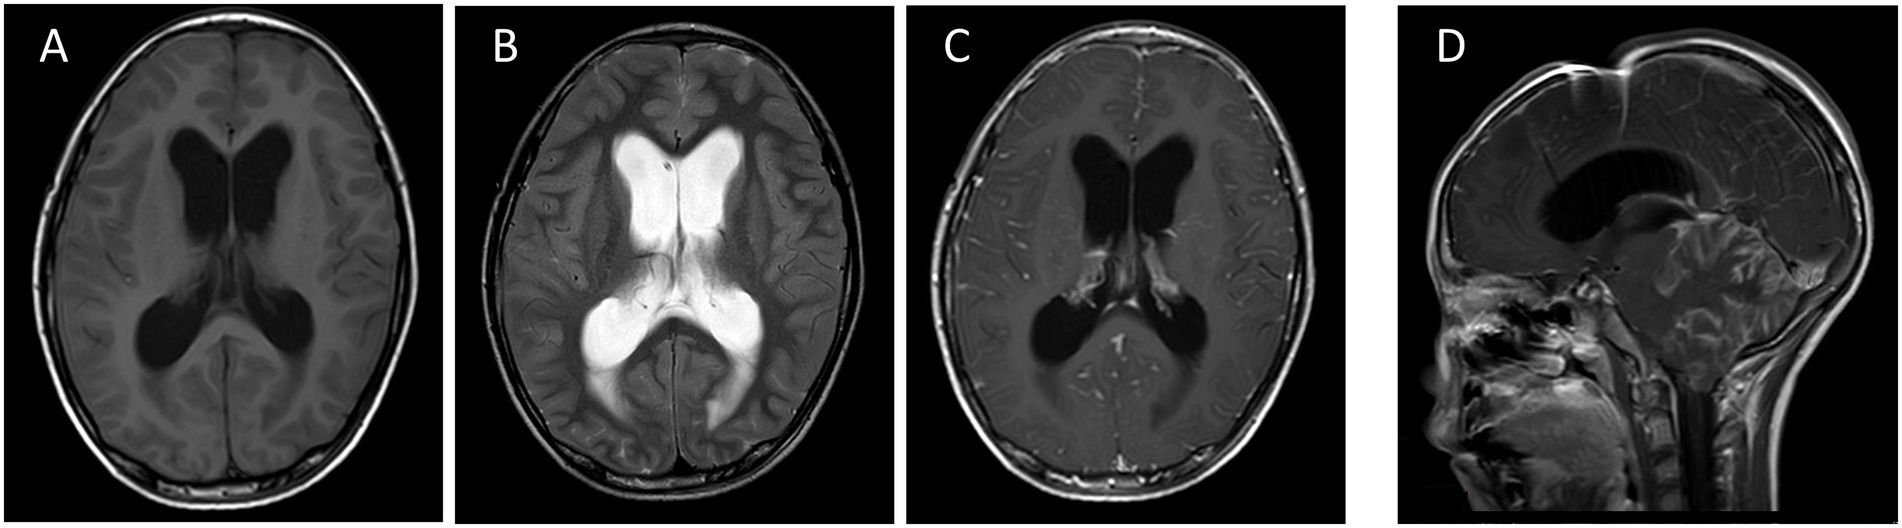

MRI revealed multiple predominantly meningeal-based enhancing lesions with diffuse abnormal signals in the bilateral cerebellar hemispheres, cerebellar vermis, and brainstem, initially suggesting a high likelihood of meningitis. Despite the extensive involvement, no definite focal space-occupying lesion was identified in the cerebellar vermis, and this atypical presentation posed the primary diagnostic challenge (Figures 2A–D).

Figure 2. Horizontal T1 (A), horizontal T2 (B) and horizontal T1 enhancement (C) images demonstrate enlargement of the supratentorial ventricular system suggestive of hydrocephalus, with extensive gyrus-like thickening and enhancement of the soft meninges predominantly present in the cerebellar hemispheres, cerebellar vermis, and brainstem bilaterally, which is combined with multiple abnormal linear enhancements of the supratentorial soft meninges, suggesting a high likelihood of meningitis. Sagittal T1 (D) still shows subcerebellar tonsillar herniation, supratentorial obstructive hydrocephalus and its post-drainage manifestations.